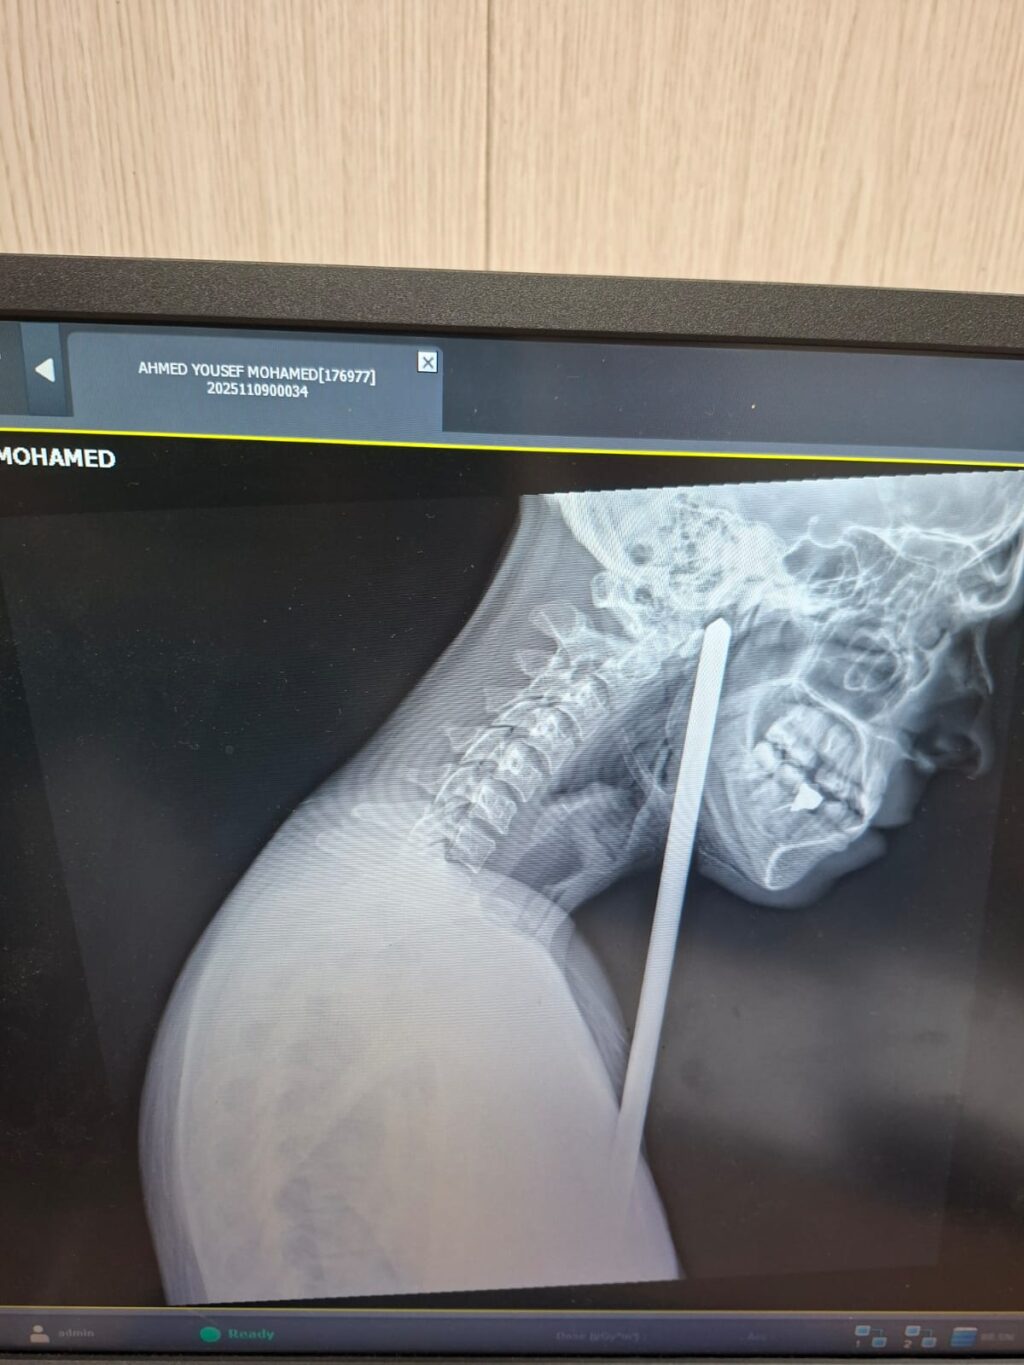

جرت الواقعة عندما وصل مريض يبلغ من العمر 24 عامًا إلى قسم الطوارئ بالمستشفى إثر تعرضه لسقوط من ارتفاع حوالي مترين، ما أدى إلى نفاذ سيخ حديدي عبر الذراع الأيمن وصولاً إلى أسفل الفك السفلي من الناحية اليسرى. كانت الإصابة صادمة ومعقدة بحيث قد تؤدي إلى مضاعفات خطيرة تمس الأعصاب والأوعية الدموية ومسار التنفس إن لم يتم التعامل معها بحرفية وسرعة. وعلى الفور تم استقبال الحالة وفق بروتوكولات الطوارئ المعتمدة، وإجراء الفحوصات والأشعة اللازمة لتحديد مسار الجسم الغريب وتقييم احتمالات النزف أو إصابة الأنسجة الحيوية.

قاد العملية الجراحية الدكتور إسلام قاسم رئيس قسم جراحة الوجه والفكين، وبمشاركة عقيد طبيب/ أمير الراوي استشاري جراحة الوجه والفكين، ود. باسل الجرواني، ود. محمد مجدي من أطباء القسم. وقد واجه الفريق تحديًا بالغًا في كيفية إزالة السيخ الحديدي دون الإضرار بالأنسجة المحيطة أو التسبب في نزف خطير، وذلك نظرًا لمرور السيخ بالقرب من أعصاب حيوية وشبكات دقيقة من الأوعية الدموية. وتمت عملية الاستخراج بحرفية دقيقة تحت تأثير المخدر الكلي وبمشاركة فريق التخدير بقيادة الدكتور سمير حسن رئيس قسم التخدير بالمستشفى.